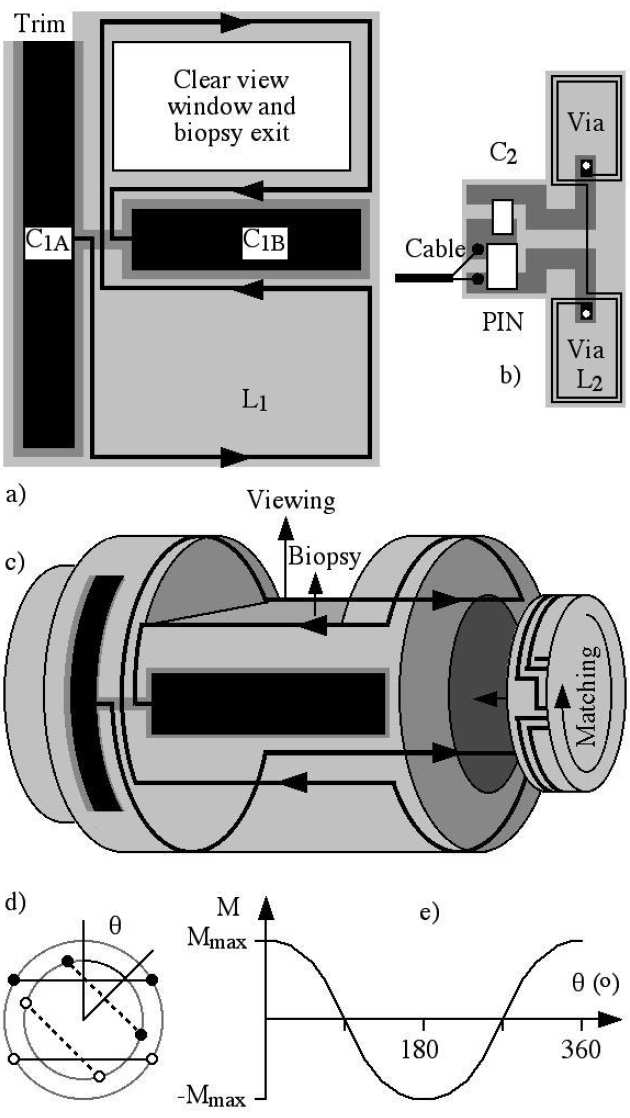

| a) external coil, b) internal coil, c) integration on duodenoscope, d) variable transformer, e) variation of mutual inductance with angle. |